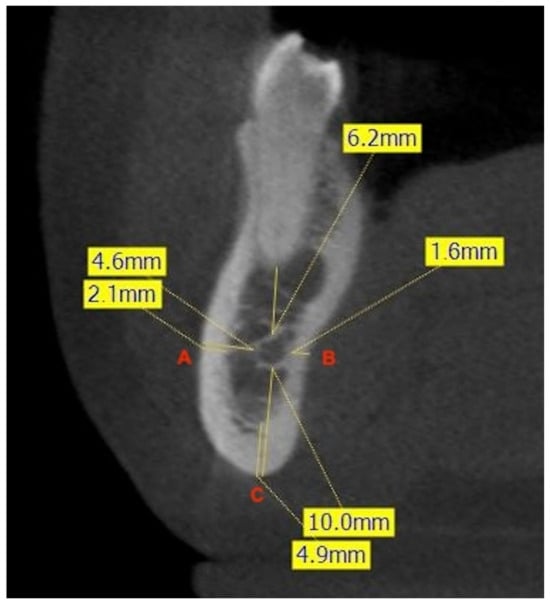

2.4. Bone Thicknesses

To evaluate the bone thickness surrounding the MC, the major axes of the mandibular teeth were fixed, and three lines were drawn to three different points. Point A was fixed on the vestibular cortex, point B on the lingual cortex, and point C on the base of the mandible. Then, the average distances from these points to the MC were measured. After this recording, cortical thicknesses were measured to differentiate between medullary and cortical bone. Thicknesses were measured in relation to the major axis of the 2MPM, in the interradicular zone of the 1M, and in the interradicular zone of the 2M (Figure 2).

Figure 2. Example of measurement of the shortest linear distances (mm) at the level of the right second premolar. The frontal CBCT image shows the distance from the most buccal (A) and lingual (B) aspects of the canal to the corresponding cortical plates of the mandible, and the minimum linear distance between the inferior aspect of the canal and the inferior border of the mandible (C). The measurement of the thickness of the cortical bone at each point is also illustrated.